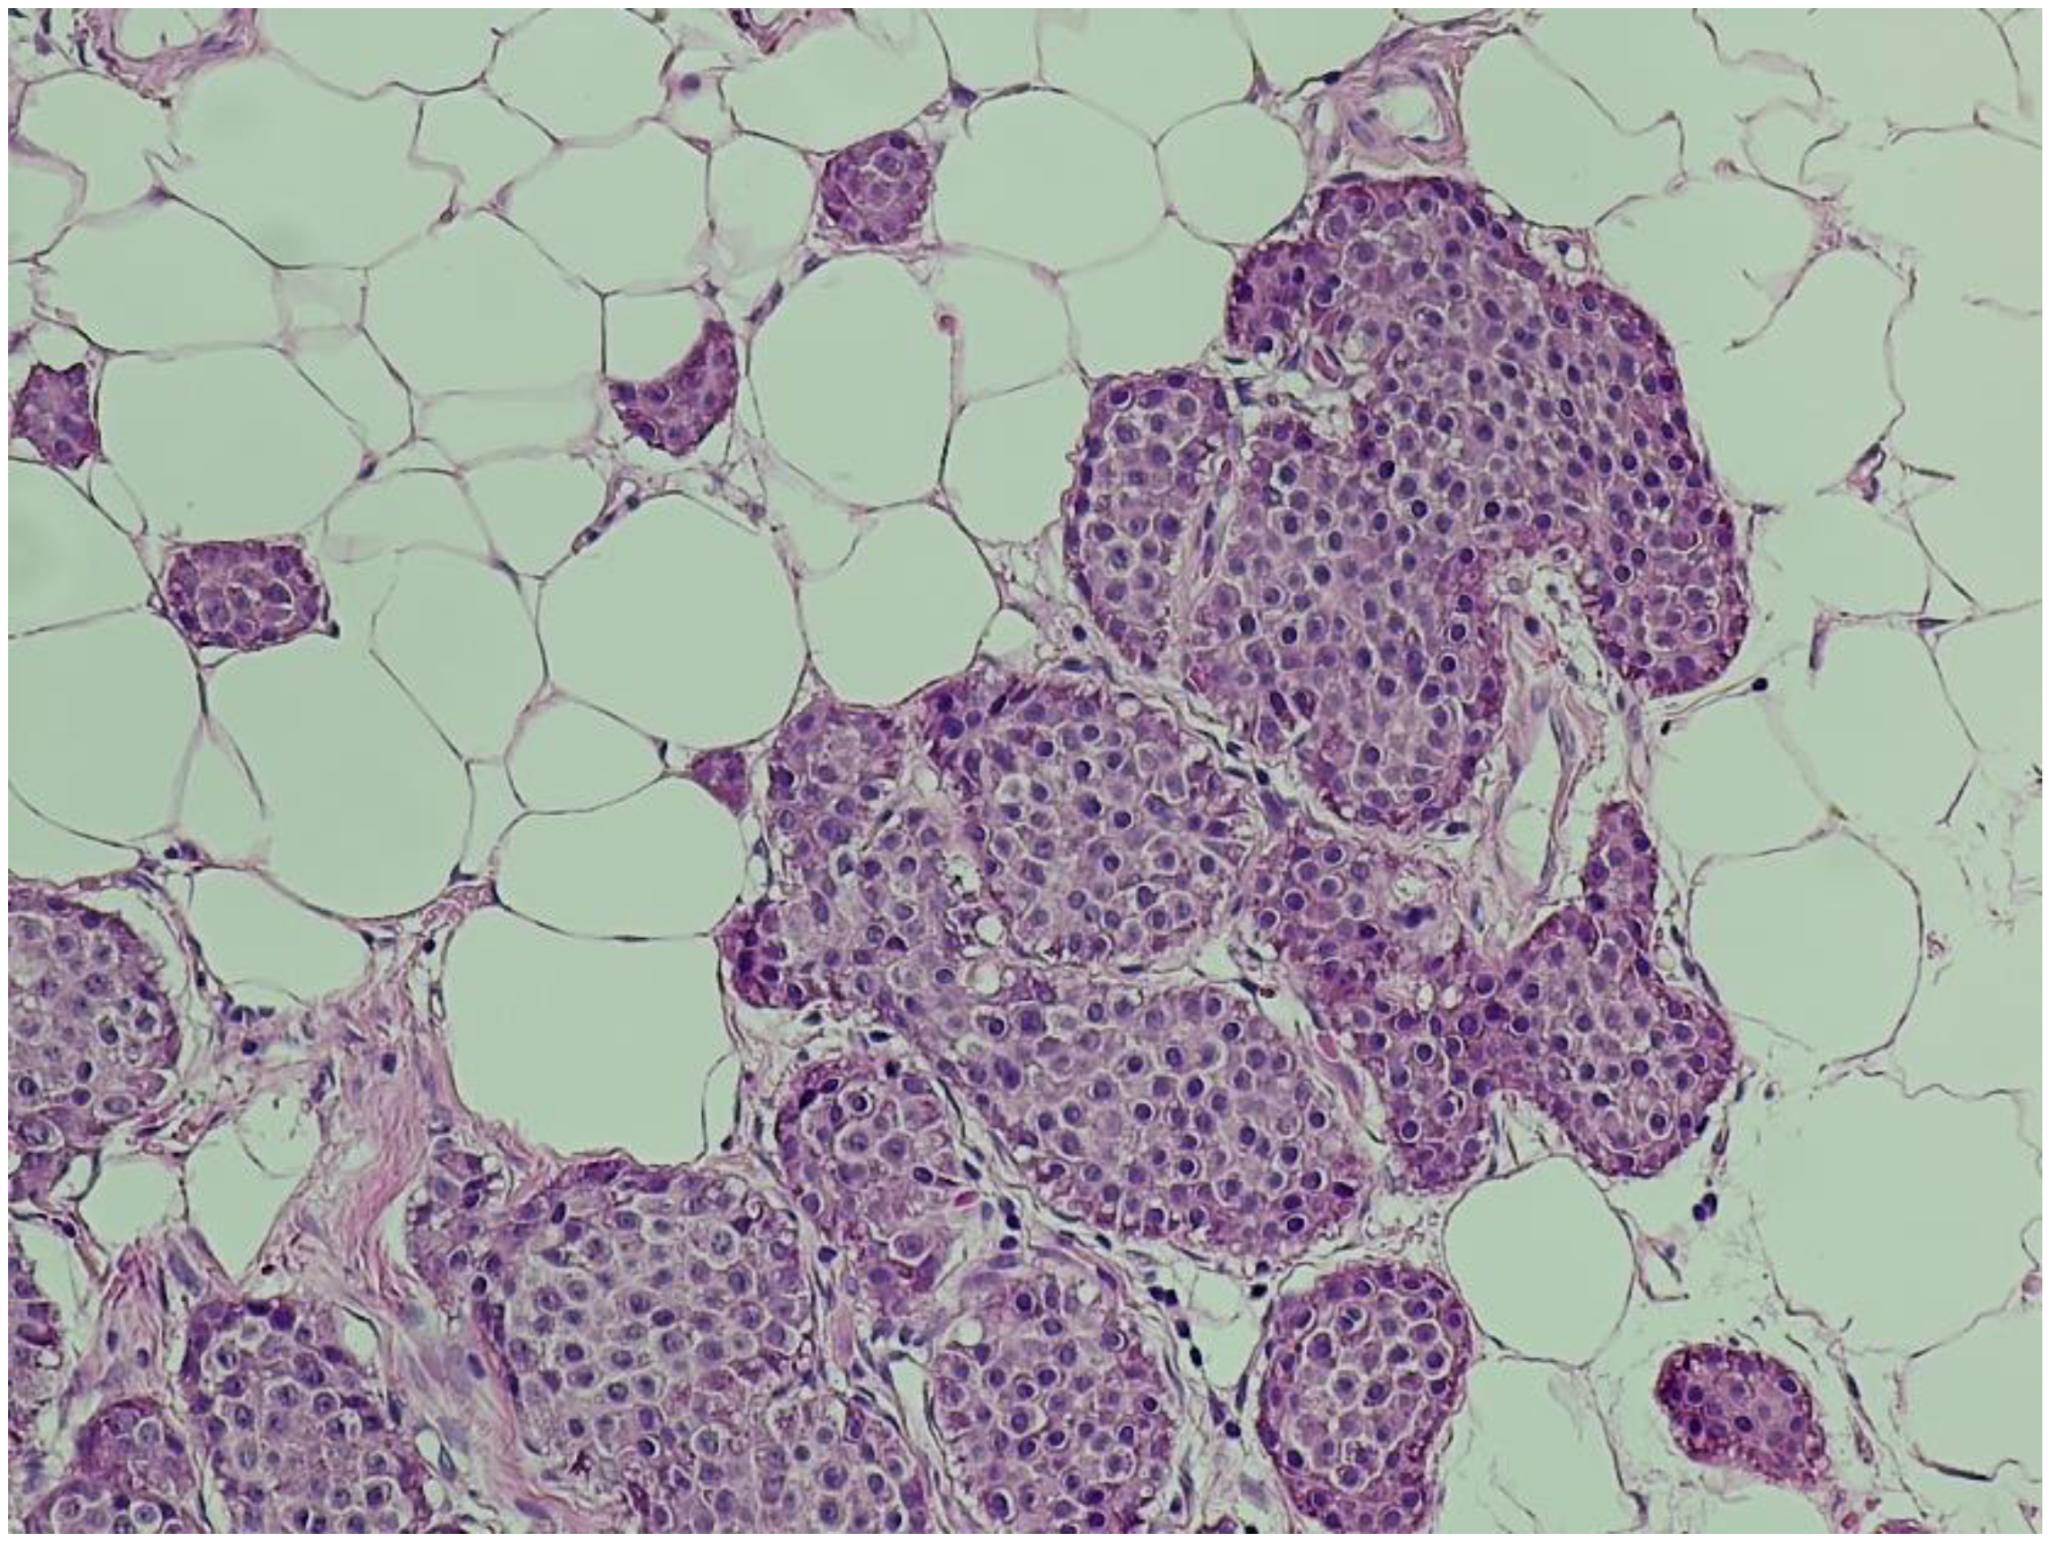

Histopathological Findings All surgical specimens were processed using standard histopathological protocols.

Hematoxylin and eosin (H&E) staining revealed a diffuse proliferation of tumor cells within adipose tissue, predominantly arranged in nested and insular patterns, with focal areas of trabecular architecture. The neoplastic cells were uniform in appearance, displaying round to oval nuclei, finely granular “salt-and-pepper” chromatin, and scant eosinophilic cytoplasm (Figure 4). Mitotic figures were rare (fewer than two per ten high-power fields), and no areas of tumor necrosis were identified—features consistent with a well-differentiated neuroendocrine tumor.

Immunohistochemistry (IHC) showed diffuse and strong positivity for chromogranin A and CD56, with focal weak staining for synaptophysin, supporting neuroendocrine differentiation (Figure 5, Figure 6, Figure 7 and Figure 8).

The Ki-67 proliferation index was estimated at approximately 3%, corresponding to a grade 2 (G2) neuroendocrine tumor according to WHO classification.

Figure 4. Hematoxylin and eosin (H&E) staining (×100). Nests of uniform neuroendocrine tumor cells exhibiting round nuclei, “salt and pepper” chromatin, and minimal cytological atypia, consistent with a well-differentiated morphology.